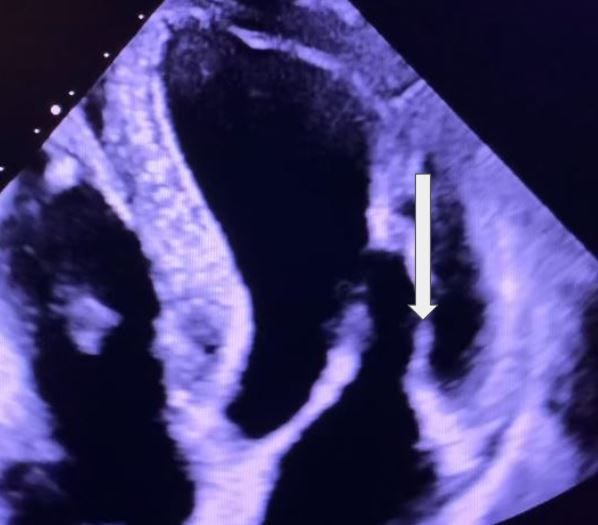

Which chamber is displayed on this parasternal long axis image?

A. Right atrium

B. Left atrium

C. Left ventricle

D. Right ventricle